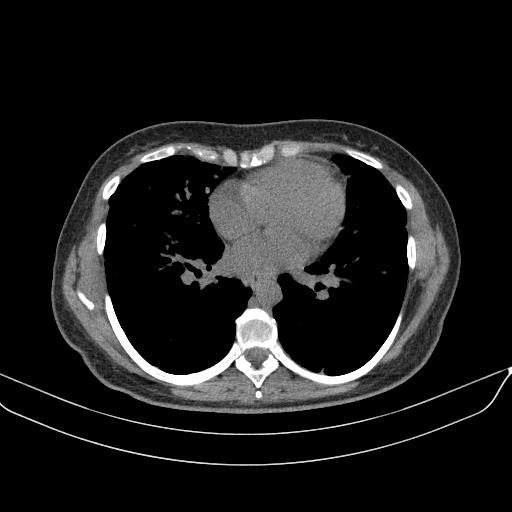

Targeted Slice 70 - Mediastinum Window Analysis (Generated vs Real Venous)

0.759

Mediastinum SSIM

45.2

Mediastinum RMSE

16.1

Mediastinum MAE

Average Mediastinum Window Metrics Across All Slices (133 slices) - Generated vs Real Venous

0.736

Mediastinum SSIM (Avg)

46.4

Mediastinum RMSE (Avg)

17.0

Mediastinum MAE (Avg)

Original VENOUS CT scan

No window - Raw intensity values

Lung window (WL -600, WW 1500 β†’ Low βˆ’1350, High +150)

Mediastinum window (WL 40, WW 400 β†’ Low βˆ’160, High +240)